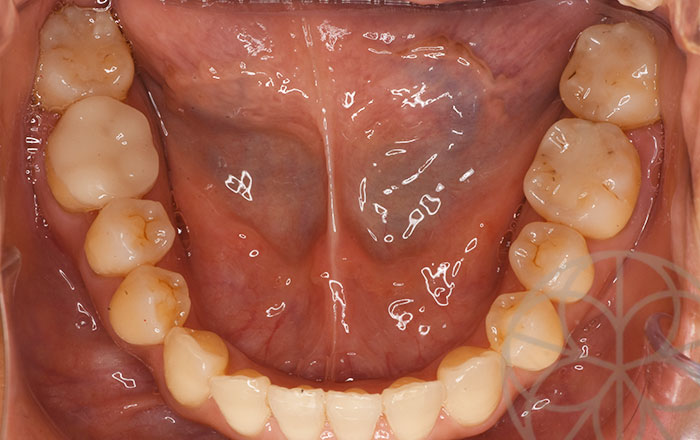

治療前状況①

前歯は少し下顎が前方に位置しており、隙間があります。

奥歯のかみ合わせも少し下顎が前に位置しており、隙間が空いている部分があります。